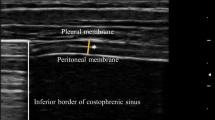

The patients were studied in the semi-recumbent position throughout the study. Ultrasonography was performed by two intensivists both experienced in ultrasonography, using an Envisor system (Philips Ultrasound, Bothell, WA) equipped with a high resolution 12 MHz ultrasound linear probe. Using the signal from the ventilator, airway pressure was displayed on the screen of the Echo-Doppler machine during NIV, ensuring accurate determination of the tracings relative to the respiratory cycle. Ultrasound recordings of diaphragm thickness were performed as previously reported [15]. Briefly, the diaphragm was located by placing the transducer in the intercostal space above the right 10th rib in the midaxillary or anteroaxillary line and directing the ultrasound beam perpendicular to the diaphragm (Fig. 1a). The zone of apposition was assessed at 0.5–2 cm below the costophrenic sinus. The inferior border of the costophrenic sinus was identified at end-inspiration as the zone of transition from the artefactual representation of normal lung (the lung sliding) to the visualization of diaphragm and liver. The diaphragm thickness was recorded in time motion (TM) mode. The sweep speed was adjusted as slow as possible to obtain a minimum of three cycles on the same image. The diaphragm was outlined by the two clear bright parallel lines of the pleural and peritoneal membranes (Fig. 1b and Online Videos). Several images were recorded and images were deemed invalid if the two clear bright parallel lines of the pleural and peritoneal membranes were not plainly identified at each moment of the respiratory cycle. Ultrasonographic recordings were stored on compact disks, and a subsequent computer-assisted quantitative analysis was performed by a trained investigator who was unaware of the ventilatory condition. The measurements included diaphragm thickness at end-expiration (T EE) and at end-inspiration (T EI). When airway pressure could not be displayed on the screen of the Echo-Doppler machine to match the ultrasound tracings to the respiratory cycle (during SB), T EE was measured just before the thickening start and T EI was measured at maximal thickening. Measurements were averaged out of three or more consecutive breaths on the last valid image recorded at the end of each period. The thickening fraction (TF) was calculated as (T EI − T EE)/T EE and expressed as a percentage (Fig. 1c).

Probe placement to explore the diaphragm in the zone of apposition (a), with the ultrasonographic view of the normal diaphragm in the zone of apposition (b) and illustration of the measurement of diaphragm thickness at end-inspiration and end-expiration in TM mode (c). T EI thickness at end-inspiration, T EE thickness at end-expiration